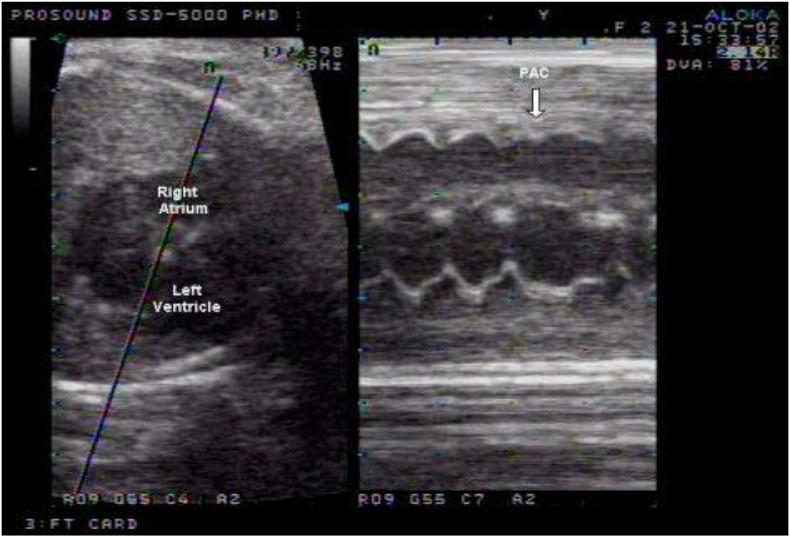

This article reviews important features for improving the diagnosis and management of fetal arrhythmias. The normal fetal heart rate ranges between 110 and 160 beats per minute. A fetal heart rate is considered abnormal if the heart rate is beyond the normal ranges or the rhythm is irregular. The rate, duration, and origin of the rhythm and degree of irregularity usually determine the potential for hemodynamic consequences. Most of the fetal rhythm disturbances are the result of premature atrial contractions (PACs) and are of little clinical significance. Other arrhythmias include tachyarrhythmias (heart rate in excess of 160 beats/min) such as atrioventricular (AV) reentry tachycardia, atrial flutter, and ventricular tachycardia, and bradyarrhythmias (heart rate <110 beats/min) such as sinus node dysfunction, complete heart block (CHB) and long QT syndrome (which is associated with sinus bradycardia and pseudo-heart block).

本文综述了改善胎儿心律失常诊断和管理的重要特征。正常胎儿心率范围在每分钟110至160次之间。如果心率超出正常范围或节律不规则,则认为胎儿心率异常。节律的速率、持续时间、起源以及不规则程度通常决定了血流动力学后果的可能性。大多数胎儿节律紊乱是房性早搏(PACs)的结果,临床意义不大。其他心律失常包括快速性心律失常(心率超过160次/分钟),如房室(AV)折返性心动过速、心房扑动和室性心动过速,以及缓慢性心律失常(心率<110次/分钟),如窦房结功能障碍、完全性心脏传导阻滞(CHB)和长QT综合征(与窦性心动过缓和假性心脏传导阻滞有关)。